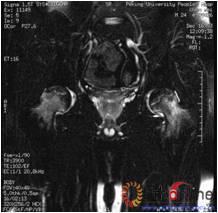

病灶修复情况比较,加用BMP2组病灶修复的完全性及硬化骨数量普遍优于未加BMP2组。(图3)

图3-1 女,31岁,SARS患者骨坏死,(1)MRI示双侧股骨头坏死,右Ⅱb(B型),左Ⅱc(C1型);(2)打压植骨术(未加BMP2)后坏死修复不完全,仍遗留股骨头软骨下病灶未完全修复, 5年随访关节功能优(Harris评分96分)